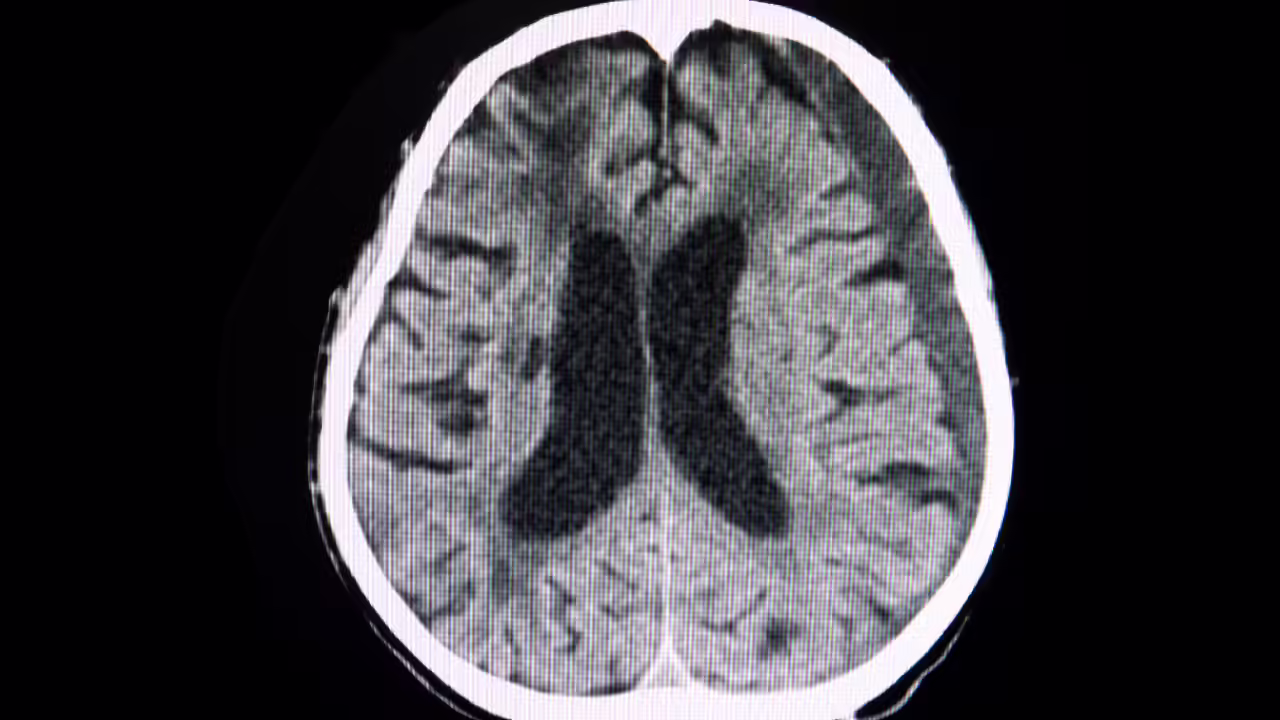

क्रिकेट, जबकि आम तौर पर एक सुरक्षित खेल है, इसमें सिर और गर्दन की गंभीर चोटों का खतरा होता है। उच्च-वेग वाली गेंद का सीधा प्रभाव कई विनाशकारी स्थितियों को जन्म दे सकता है।एपीड्यूरल हिमाटोमा: यह तब होता है जब खोपड़ी और मस्तिष्क के बीच रक्तस्राव जमा हो जाता है। दबाव तेजी से बढ़ता है, अगर तुरंत इलाज न किया जाए तो संभावित रूप से बेहोशी या मृत्यु हो सकती हैसबड्यूरल हेमेटोमा: ड्यूरा मेटर (यानी मस्तिष्क का बाहरी सुरक्षात्मक आवरण) के नीचे रक्तस्राव मस्तिष्क के ऊतकों को संकुचित कर सकता है और महत्वपूर्ण न्यूरोलॉजिकल कार्य को बाधित कर सकता हैसबराचोनोइड रक्तस्राव: मस्तिष्क की सतह पर एक प्रकार की टूटी हुई रक्त वाहिका आसपास के स्थान में बाढ़ ला देती है, जिससे अक्सर तत्काल हस्तक्षेप के बिना घातक परिणाम होते हैं।फैलाना एक्सोनल चोट: उच्च प्रभाव वाला आघात जो मस्तिष्क के ऊतकों में सूक्ष्म दरारें पैदा कर सकता है, जिसके परिणामस्वरूप गंभीर तंत्रिका संबंधी क्षति हो सकती है।मस्तिष्क में प्रवेश के साथ खोपड़ी का फ्रैक्चर: हड्डी के टुकड़े मस्तिष्क में छेद कर सकते हैं या उसे संकुचित कर सकते हैं, जिससे अपरिवर्तनीय क्षति हो सकती है।ये चोटें विशेष रूप से खतरनाक होती हैं, क्योंकि इस प्रकार की चोटों में तुरंत होने वाले कोई स्पष्ट लक्षण नहीं होते हैं, जो तेजी से चिकित्सा देखभाल और साइट पर तैयारियों के महत्व पर जोर देते हैं। (ये निष्कर्ष ऑस्ट्रेलिया के मेडिकल जर्नल में उल्लिखित हैं)